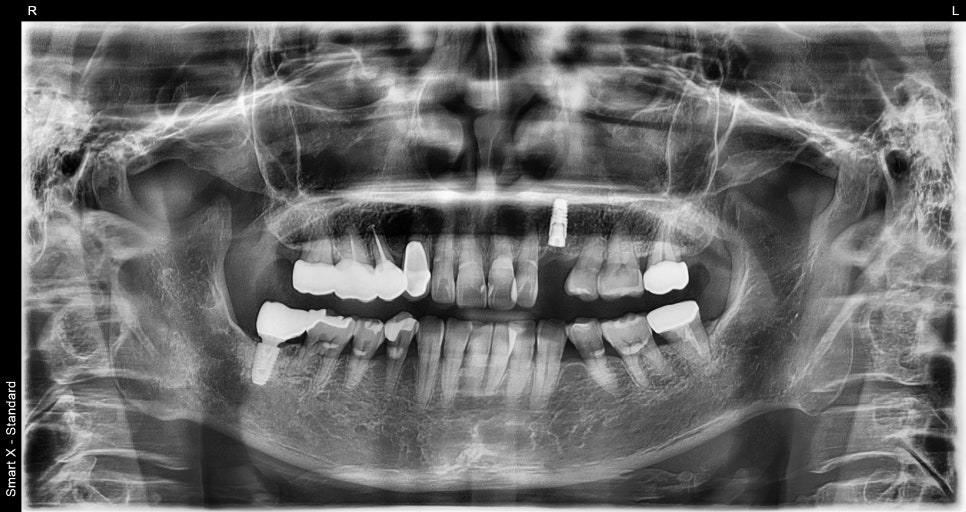

📸 파노라마 엑스레이

골수염(Osteomyelitis) 환자분 초진 엑스레이